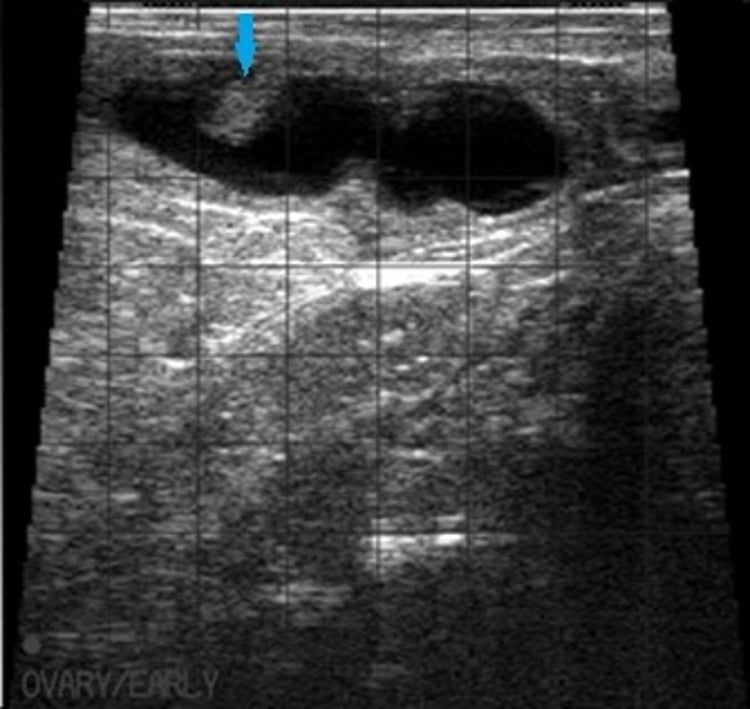

This ultrasonographic image shows a bovine embryo within black uterine fluid (arrow) at 32 days gestation.

Courtesy of Dr. Jonathan Statham.

Nonpregnant cows can be identified earlier (28–32 days after breeding), and the status of the ovaries and uterus can be determined.

The viability of the embryo or fetus can be assessed—eg, by visualization of a fetal heartbeat.